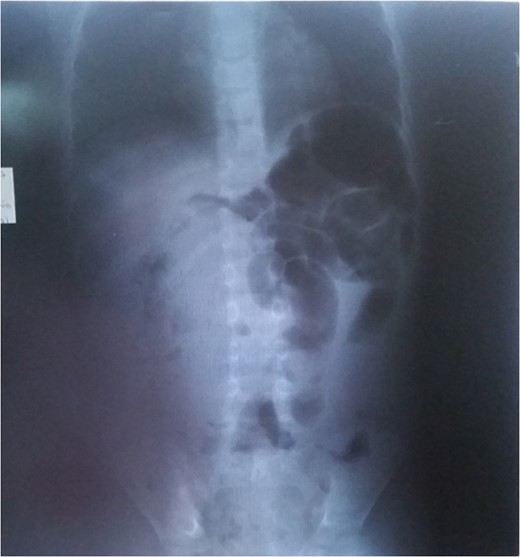

We report the case of a 6-year-old boy who presented at the Emergency Room (ER) of our institution with severe abdominal pain and vomiting. History of presenting complain revealed that one week prior to the consultation, the patient started complaining of intense and progressive pain, initially epigastric but later peri-umbilical. The pain was paroxysmal, without any irradiation and no remitting or exacerbating factor. Three days after the onset of the pain, there was a complete stoppage of stool passage with vomitus which initially was food and later biliary. This prompted the personal administration of Albendazole by the mother but with the persistence of the clinical picture she rapidly brought the child the ER. The past-history was non-contributory. Upon arrival, the patient was anxious, and physical exam revealed a conserved general state, stable vitals, an obstructive syndrome, an irregular umbilical mass, with no abdominal distention and no signs of dehydration. A plain abdominal radiograph revealed an agglutination of distended colonic segments in the left upper quadrant (Fig. 1). An abdominal ultrasound was also conducted and showed a cystic abdominal mass. Complete blood count revealed moderate anaemia. Horizontal laparotomy was done and found a twisted small bowel obstruction with a large encapsulated yellowish mass inserted with a small base on the anti-mesenteric aspect of the ileum measuring 10×15 cm2 at 30 cm away from the ileo-colic junction without any adhesions. On the same insertion but rather on the mesenteric aspect was a smaller greenish mass (3 × 5 cm2) giving a granulated feeling on palpation. There also were numerous lymph nodes on the mesentery. Small bowel bulk resection of 10 cm was done and intestinal end-to-end anastomosis also. Histopathology confirmed the mesentery lipoma and the associated structure to be a myxoma. Post-operative progress notes return of peristalsis and stool from Day 3 post-op (Fig. 2).

Lipomas rarely call for concern since they often are superficially located and only give rise to aesthetic worries from patients. When lipomas are located intra-abdominally, the symptoms more often are vague and often misleading. The diagnosis of mesenteric lipomas is usually incidental but children may present with abdominal pain, vomiting, abdominal distention and rarely with intestinal obstruction as was observed in our case who presented with intestinal obstruction syndrome. When the tumour is located closest to the intestinal lumen, due to compression, it gives rise to obstructive symptoms but allows peristalsis progression of the bowel [8]; this is different from what we observed with a complete volvulus and progressively increasing pain (Fig. 2).